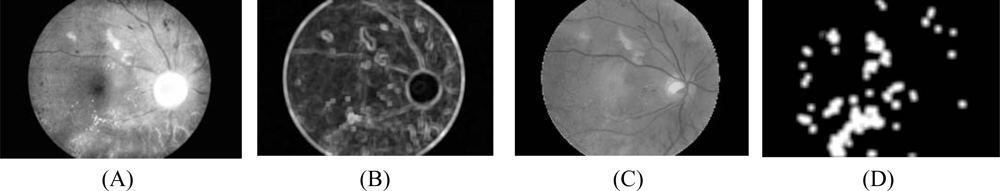

- Intensity image after pre-processing (ICLAHE) is selected as one of the classification features because exudate pixels can usually be distinguished from normal pixels by their intensity. Firstly, the Red, Green and Blue (RGB) space in the original image is transformed to Hue, Saturation and Intensity (HSI) space. A median filtering operation is then applied on the I (intensity) band to reduce noise before a Contrast-Limited Adaptive Histogram Equalization (CLAHE) is applied for contrast enhancement [23]. The original intensity band image and intensity band after preprocessing are shown in Figures 1A and 1B, respectively.

- Standard deviation of ICLAHE is also chosen as an input parameter because distribution measurement of the pixel values would differentiate exudate area from the others since standard deviation shows the main characterization of the closely distributed cluster of exudates. The standard deviation of the intensity bands after preprocessing is shown in Fig. 1C. Standard deviation is defined in Equation 6:where x is a set of all pixels in a sub-window W(x), N is a number of pixels in W(x), μICLAHE (x) is mean value of ICLAHE(i) and i∈W(x). A window size of 15 × 15 pixels was used in this step.

- 4.5 A number of neighboring white pixels of the resulting image from the process 4.1 – 4.4 is counted using a window size of 17 × 17 to form our final feature, namely an image of the number of edge pixels as shown in Figure 3D:where area is the number of pixels in the region and perimeter is the total number of pixels around the boundary of each region.